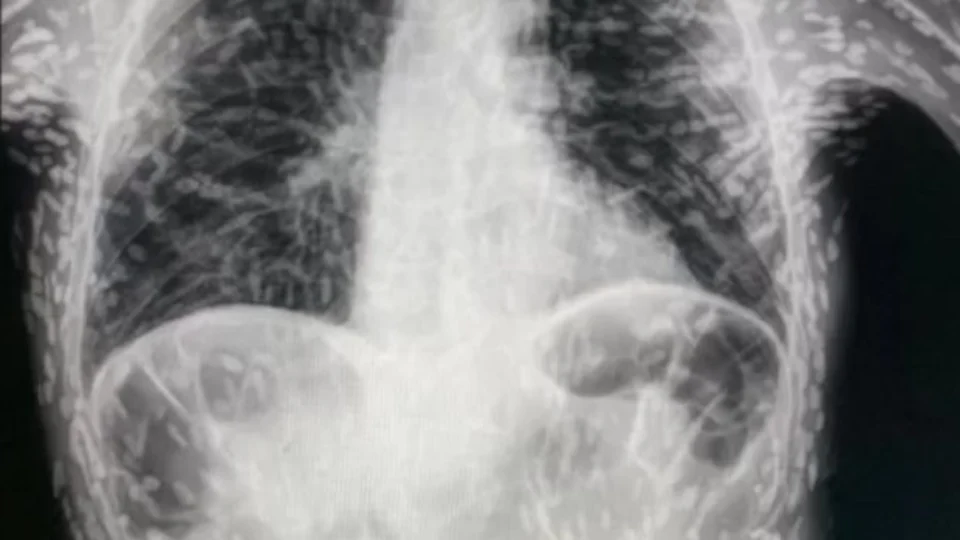

O médico paulista Vitor Borin de Souza viralizou, desde domingo (18), uma postagem no Twitter com exame do tórax de um paciente repleto de ovos de tênia.

Vitor explicou que o quadro envolvia um diagnóstico de cisticercose, com apresentação de tosse constante há dois meses.

Ele ressalta que nas imagens é possível perceber que os ovos de tênia localizados no corpo já estavam mortos, calcificados, e não apresentavam riscos.